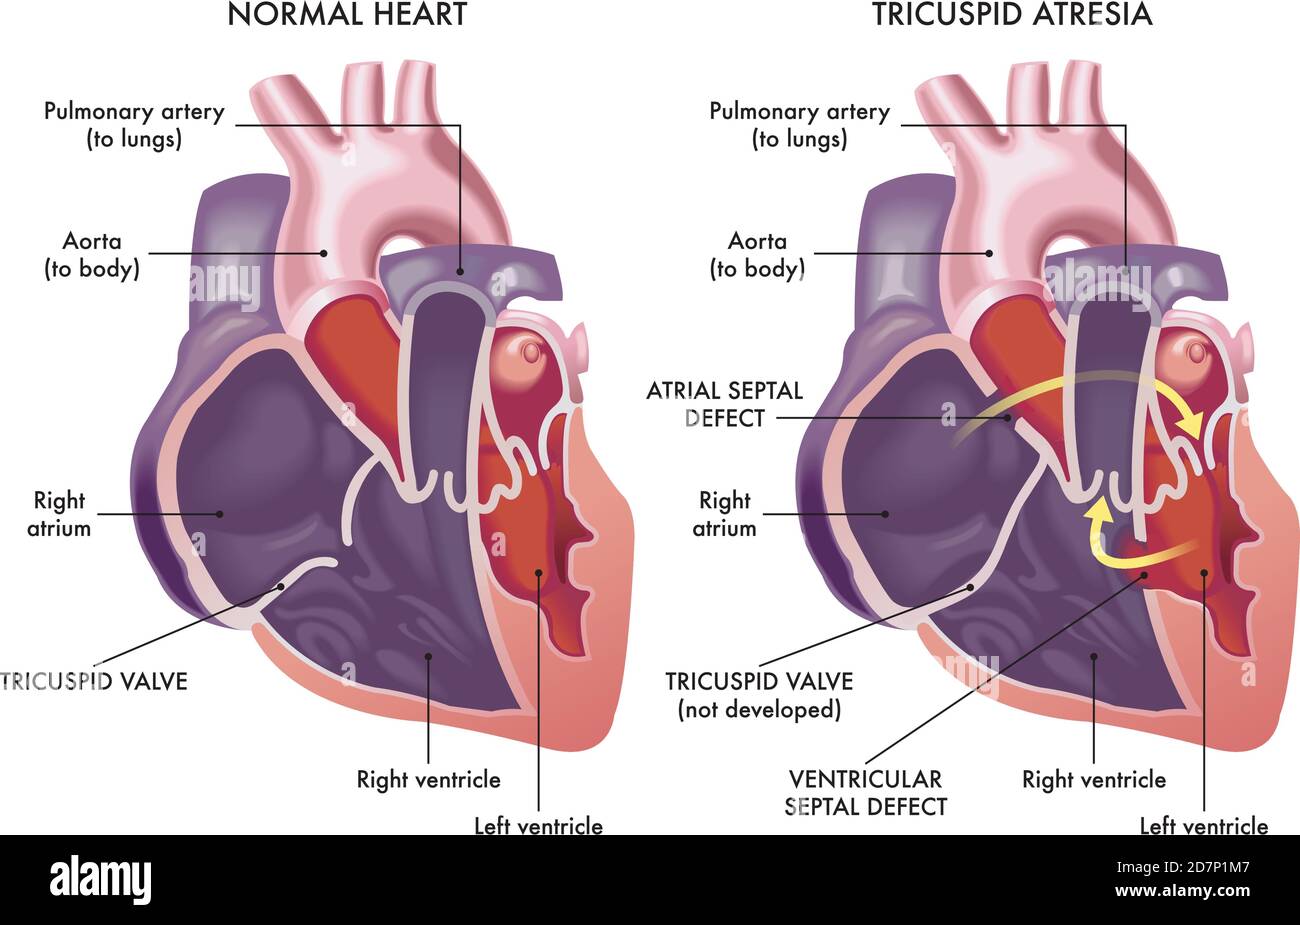

Medical illustration that compare a normal heart with a heart affected by cardiac defect called Tricuspid Atresia, with annotations. Stock Vectorhttps://www.alamy.com/image-license-details/?v=1https://www.alamy.com/medical-illustration-that-compare-a-normal-heart-with-a-heart-affected-by-cardiac-defect-called-tricuspid-atresia-with-annotations-image383414983.html

Medical illustration that compare a normal heart with a heart affected by cardiac defect called Tricuspid Atresia, with annotations. Stock Vectorhttps://www.alamy.com/image-license-details/?v=1https://www.alamy.com/medical-illustration-that-compare-a-normal-heart-with-a-heart-affected-by-cardiac-defect-called-tricuspid-atresia-with-annotations-image383414983.htmlRF2D7P1M7–Medical illustration that compare a normal heart with a heart affected by cardiac defect called Tricuspid Atresia, with annotations.